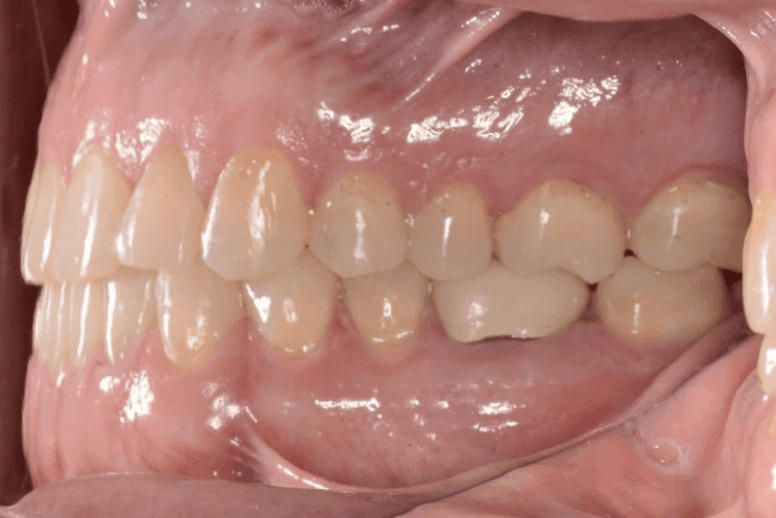

Final results

INTRAORAL